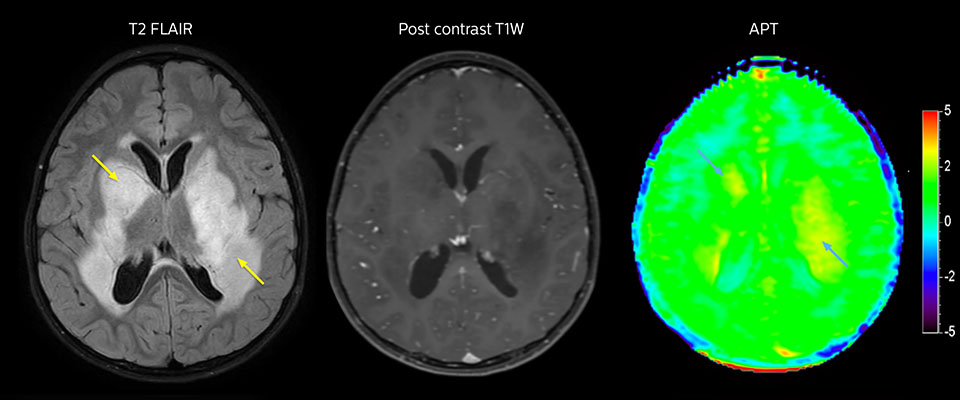

APT imaging of low-grade tumor

Low-grade glioma in a 5-year-old patient with neurofibromatosis 1. This low-grade lesion does not enhance on the post-contrast images, but does show an intermediate APT signal. The lesion stability over time confirms that it is a low-grade pathology.